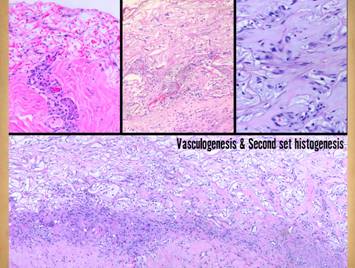

Left upper, Integra on a thigh.  The matrix as seen through the silicone is regenerated properly into a neodermis.  In a seam between two pieces of Integra, a small open gap has resulted in normal wound healing, recognized by the bead of granulation tissue that has arisen.  Left lower, a similar situation in another patient.  The Integra reconstructed skin is flat and soft and of normal color.  In the center is a hypertrophic scar where the gap between Integra edges allowed normal wound healing.  Center upper, an old trauma scar across the ankle.  Scar is resisting movement and becoming more tendinous and stiff, causing the scar to fracture and ulcerate from normal ankle motion which in turn perpetuates the scar, inflammation, and ulcer.  Center lower, Integra reconstructed skin on the dorsum of the hand following trauma.  Just a few weeks after skin graft placement, the neodermis is soft, compliant, and pliable to a degree comparable to normal skin.  Right, a microscopic view of regenerating Integra.  The dissimilarities of scar and Integra were seen on the last panel.  This view shows a syncytial cluster, a histologic structure that is seen in embryonic dermatogenesis and in Integra regeneration, but never in normal post-inflammatory wound healing.  This structure, explained on subsequent panels, is the basis for Integra’s biological, mechanical, and clinical properties

Pictured is matrix regeneration within a piece of Integra collagen-gag matrix.  It is no longer the non-living empty matrix placed on the original wound, but a fully restored living material.  The details of this process are now presented.  However, even without knowing the specific details, it can be appreciated that the structure, morphology, and patterns of this regenerated biological material are different than the microscopic structure of the normal post-inflammatory wound.  Normal wound healing is triggered by inflammation and then evolves according to its own “program” of how angiocytes and fibroblasts rebuild a stroma of blood vessels and connective mesh.  Integra suppresses inflammation, and thus the normal “wound healing program” is never turned on.  Integra “heals” by a fundamentally different mechanism analogous to embryonic tissue generation.  Its build to a state of complete regeneration is uniform throughout the matrix, distributed rather than stratified, and when complete, it has created a new material that has characteristics mostly like normal dermis and quite unlike scar.  The matrix coaxes the same two cells, angiocytes and fibroblasts, to make a new tissue of blood vessels and connective mesh in a patterned morphology that is profoundly different then scar.  The same cells, making the same elemental components, assemble them in a completely different pattern than wound healing and scar because the embryogenesis-and-stromal-generation “program” is entirely different than the healing-and-scar “program”.